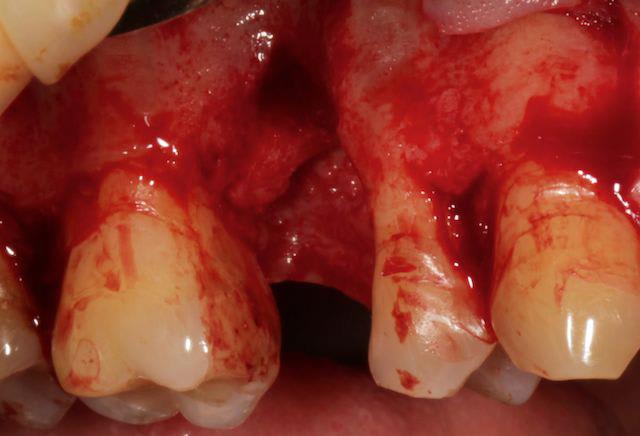

tiens pour faire avancer le débat un cas de ROG verticale et horizontale, avec membrane PTFE armé titane.

à la mandibule, non je n'ai pas fait de photos avec la membrane, trop compliqué dans ce cas là, surtout pour ce qu'en fait, j'ai mis un mélange bio-oss autogéne à 50/50 le tout recouvert par un bio-gide securisée par des pin's.